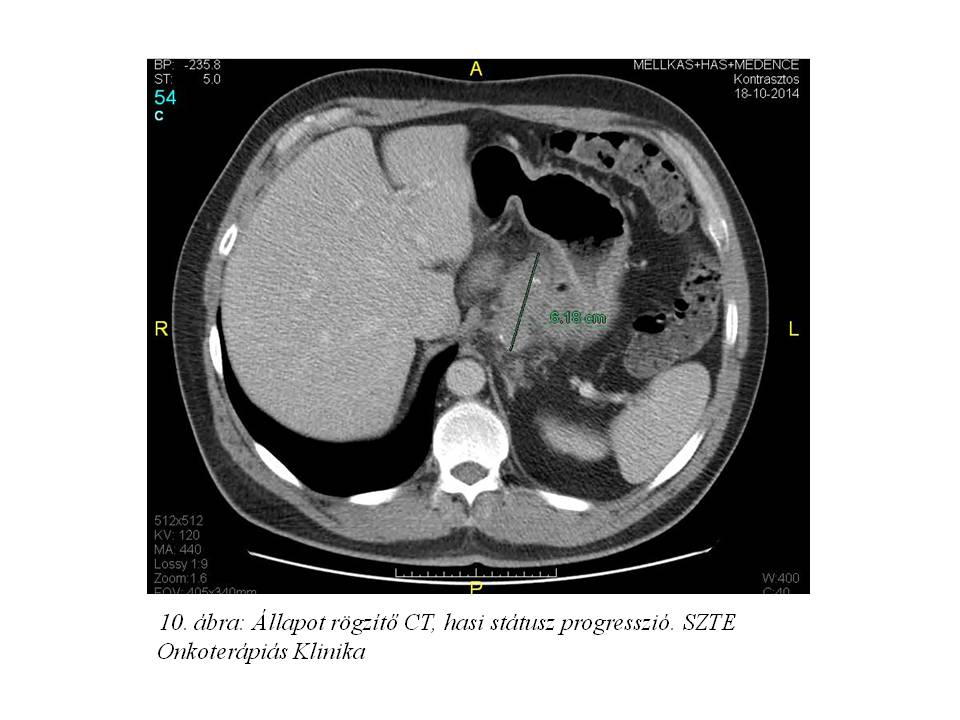

2014.05.15-én gasztro-intestinális onkoteam a tumor elhelyezkedése miatt a folyamat operábilissé válását nem tartotta valószínűnek, és további palliatív onkológiai kezelést javasoltak. A felépülést követően státuszrögzítő CT-vizsgálat történt (2015.10.18. 10. ábra), mely a hasi státusz progresszióját írta le, de távoli metasztázis nem igazolódott. A folyamat aktiválódását jelezte az is, hogy az acantosis nigricans ismét aktiválódott. A beteg általános állapotát és kérését figyelembe véve, 2014.11.10-12.19-ig definitív/konverziós célú sugárkezelést adtunk a GEJ tumorra (célterület 11. ábra), a perigastricus térre, a truncus coeliacus nyirokrégióra, a lép- és májkapu, paraaorticus régióra; az 1. és 5. héten 5FU+leucovorinnal sugárérzékenyítve. A sugárkezelés megkezdésekor vérképét vörösvértest transzfúzió adásával rendeztük, ezt követően vérképe stabil volt, egyéb mellékhatás nem jelentkezett.